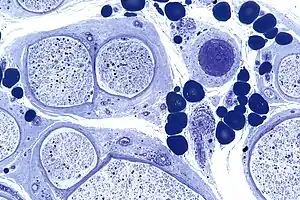

| Micrograph showing a vasculitic peripheral neuropathy; plastic embedded; Toluidine blue stain | |